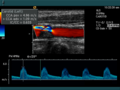

Die Aussagekraft der Sonografie kann erheblich durch die Anwendung des Doppler-Effekts erhöht werden. Man unterscheidet eindimensionale Verfahren (Pulsed-Wave-Doppler, Continuous-Wave-Doppler, auch als D-mode bezeichnet) von zweidimensionalen, farbkodierten Anwendungen (Farbdoppler – F-mode). Die Kombination B-Bild mit Pulsed-Wave-Doppler (PW-Doppler) nennt man auch Duplex.[4]

Doppler-Verfahren werden benutzt zur Bestimmung von Blutfluss-Geschwindigkeiten, zur Entdeckung und Beurteilung von Herz(klappen)fehlern, Verengungen (Stenosen), Verschlüssen oder Kurzschlussverbindungen (Shunts).

Bei der farbkodierten Doppler-Sonografie wird für einen großen Bereich eines konventionellen Ultraschallbildes (Color-Window) die örtliche Doppler-Frequenz (= mittlere Flussgeschwindigkeit) und deren Schwankungsbreite bestimmt. Damit möchte man die Turbulenz der Strömung abschätzen. Aufgrund der statistischen Bewegungen der Streuteilchen ist die Schwankungsbreite der Fließgeschwindigkeit jedoch stets größer als die Turbulenz. Das Ergebnis wird in Falschfarben auf dem B-Bild überlagert, also in Farbtönen von rot und blau für verschiedene Blutgeschwindigkeit und grün für Turbulenz. Hierbei steht üblicherweise die Farbe Rot für Bewegung auf den Schallkopf zu, während mit blauen Farbtönen Flüsse weg von der Sonde codiert werden. Bereiche der Geschwindigkeit 0 werden durch die Elektronik unterdrückt.

-

Anwendung des Doppler-Verfahrens bei einer Herzuntersuchung: Mitralklappeninsuffizienz -

Farb-Doppler und PW-Doppler. Innerhalb der Stenose ist wegen der hohen Flussgeschwindigkeit und des resultierenden Alias-Effekts die Geschwindigkeit in Blau kodiert. -